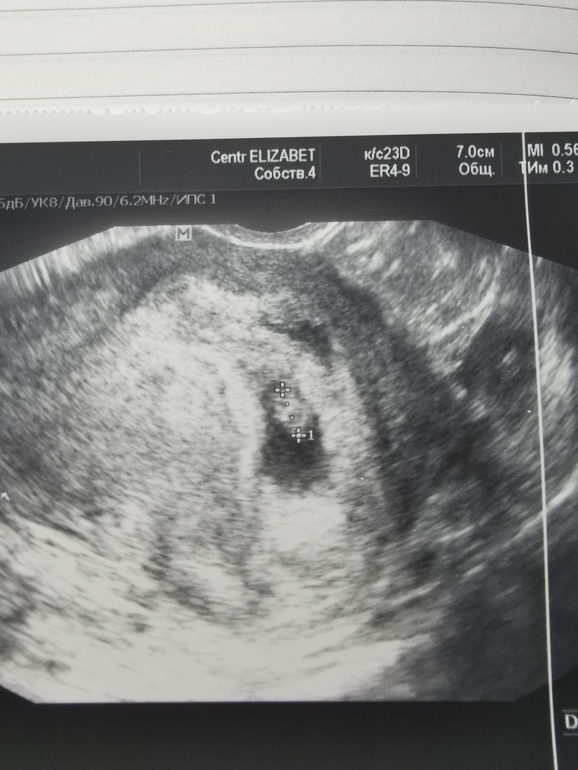

6 недель и 3 дня. ❤️❤️❤️

Сегодня весь день переживала, со вчерашнего дня пропал токсикоз. И конечно же мысли, конец света.)) Это я так свой беременный дзен словила. Хотя планировала на узи только в пятницу первое сделать. Девочки, все у нас в срок. Мы 6,6 мм, крошки. Сб есть, но слушать не давали, сказали, все хорошо. Я так рада, в прошлом году была зб на сроке 5 недель. Сейчас верю в кроху свою. Ну и фото, не знаю, кто-то по методу Рамзи поймёт кто это. А так всем беременным лёгкой беременности и меньше нервов, токс может придти, и уйти на несколько дней. А всем кто ждёт 2 полоски, апчхи🙏🙏🙏🙏🙏🙏🤰🤰🤰❤️❤️❤️❤️❤️❤️❤️

По Рамзи вроде девочка будет))))